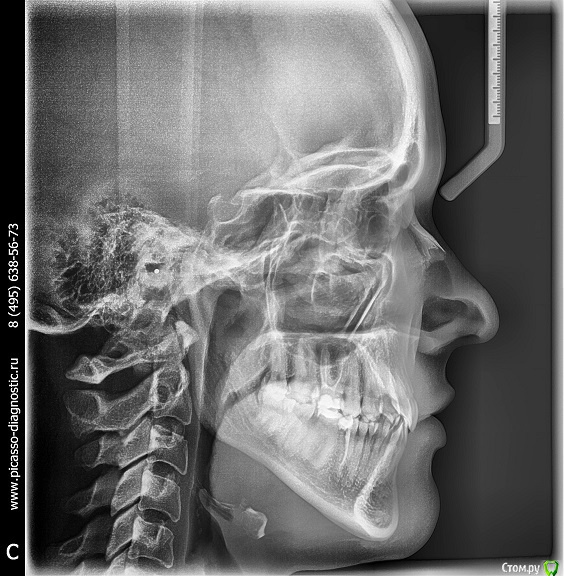

zimazima Опубликовано 20 ноября, 2015 Поделиться Опубликовано 20 ноября, 2015 Добрый вечер!Опытные ортодонты, скажите, пожалуйста, будет ли необходимо в моем случае удалять нижние 4ки? Какова вероятность того что НЧ выйдет вперед после ношения брекетов? предыстория: в 17 лет носила брекеты на ВЧ, т.к. слева клык рос поверх ряда удалили 4ку и поставили на ее место клык...при этом ВЧ потеряла симметрию((и кажется что проявилось это спустя годы (сейчас мне 30). и теперь за счет того что НЧ не ровнялась зубы начали разворачиваться опять... вопросы:- какова вероятность того что удаление нижних 4к не потребуется при лечении?(ортодонт говорит что можно поносить пол года и посмотреть в процессе, имеет ли это смысл? или лучше не терять время, может все очевидно?...)- можно ли оставлять 8ки?- реально ли вернуть центр ВЧ на место если удалить 4ку слева?- при удалении нижних и верхних 4к как сильно сузится лицо и подбородок станет ли еще более выпирающим? (лицо у меня и без того узкое и длинное, достаточно большой нос картошкой и выступающий подбородок) не станет ли хуже?- не будет ли после лечения других проблем с искривлением лица (оно у меня сейчас не симметричное - глаза на разном уровне))), на фото вижу особенно это(( в общем в жизни не так вроде бы все и плохо выглядит - на фото просто кошмар - сама посмотрела и уже готова на все.волнуюсь не будет ли хуже в моем случае? очень благодарна за любые ответы - советы - комментарии! спасибо!выложу доп фото по запросу любые нужныеЗлобина А.В. Заключение.pdf Ссылка на комментарий

m.d.n Опубликовано 21 ноября, 2015 Поделиться Опубликовано 21 ноября, 2015 эммм ну можно тут по разному работать. внизу кроме 8 ничего неудалял бы вообще. если побыстрее то слева 4. если не торопитесь то все 8 удалить открыть место под удаленный премоляр вернуть центры и имплант вместо ранее удаленного .как то так Ссылка на комментарий